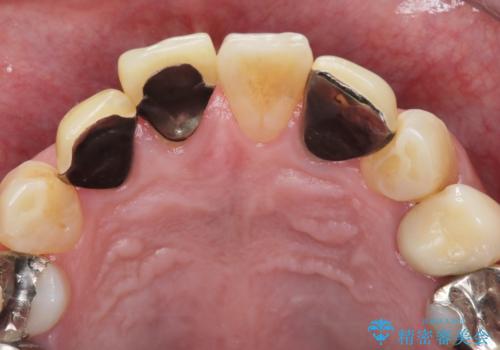

- 「被せ物の色が気になる」を主訴に来院された患者さんです。

保険で治療した被せ物が劣化し色も変色をおこしていました。かつ被せ物と歯の境目(適合)も合っていない状態でした。

被せ物の適合が悪く劣化もおこし色が変色している状態でした。そのため他の歯とも色が合っていませんでした。古い被せ物を除去し形を整えた後にオールセラミッククラウンで治療を行いました。

根っこの先端に病巣(根尖性歯周炎)があったため根管治療または抜歯してインプラントを提案しましたが、患者さんのご希望により被せ物の治療のみを行いました。